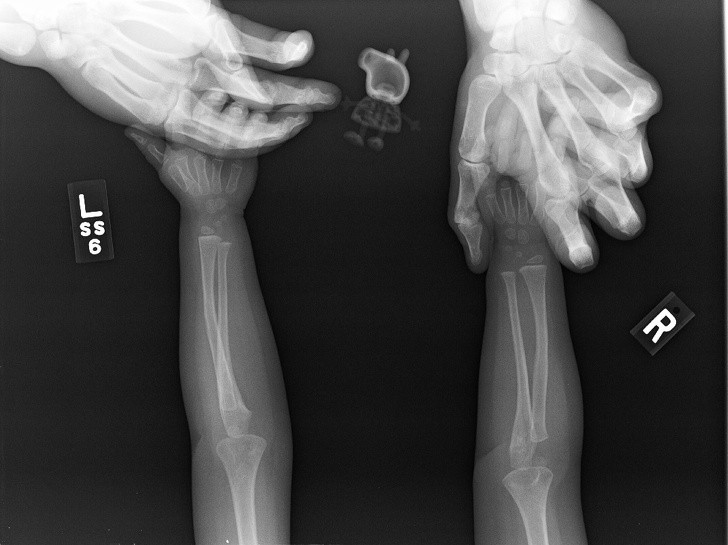

Humans are truly strange creatures and incredibly bizarre things can happen to us. These x-rays will shock even those who think they've seen it all.

X-ray it is one of the best inventions of mankind and in some situations it is indispensable. Especially because it often happens that people, especially children, they swallow objects that are not part of their daily diet. Not to mention the dogs who try to chew everything in sight and thus often end up swallowing inappropriate things.

Radiologists are already quite accustomed to seeing on X-rays strange things and some of these that we have collected for you in the gallery did not surprise them at all. Here is 15+ hacked and sometimes shocking x-rays.